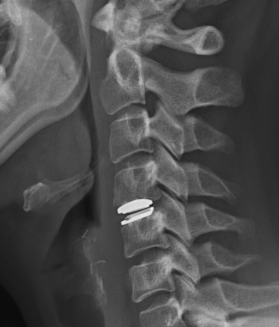

ACDA / Disc replacement

Advantage

Theoretically maintain some motion and preserve other disc segments

Technique

Depuy Discover Medtronic Prestige

Complications

Specific

- anterior displacement

- posterior displacement and spinal cord injury

- subsidence 3% - higher risk if remove or disrupt end plates

- osteolysis

- implant failure

- heterotopic ossification